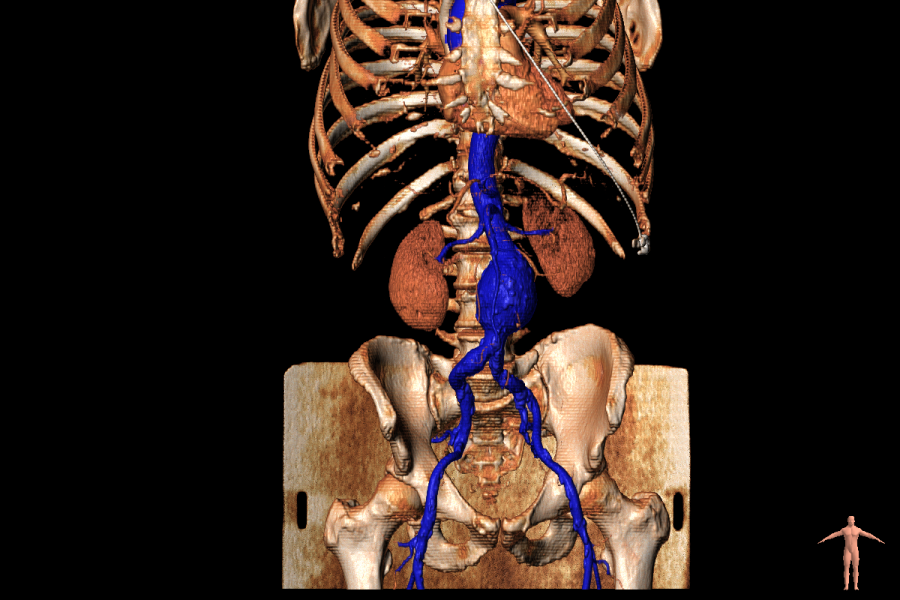

Η μεγάλη εξέλιξη των ενδαγγειακών μοσχευμάτων έχει καταστήσει δυνατή την αντιμετώπιση του συνόλου σχεδόν των διαφορετικών αορτικών ανευρυσμάτων. Ανευρύσματα της θωρακικής αορτής, θωρακοκοιλιακά ανευρύσματα και κοιλιακά ανευρύσματα που περιλαμβάνουν τις σπλαχνικές αρτηρίες, αποκαθίστανται με ενδομοσχεύματα ειδικής παραγγελίας. Μία αξονική τομογραφία χρησιμοποιείται για τον σχεδιασμό εξειδικευμένου μοσχεύματος με τη βοήθεια ειδικού λογισμικού, σύμφωνα με την μορφή και την ανατομία της αορτής του κάθε ασθενούς. Το μόσχευμα αυτό κατασκευάζεται και τοποθετείται στο εσωτερικό της αορτής με επέμβαση που πραγματοποιείται στην υβριδική αίθουσα

Τα αγγεία που φεύγουν από την αορτή και δίνουν αίμα στα διάφορα όργανα, έχουν διαφορετική ανατομία σε κάθε ασθενή.